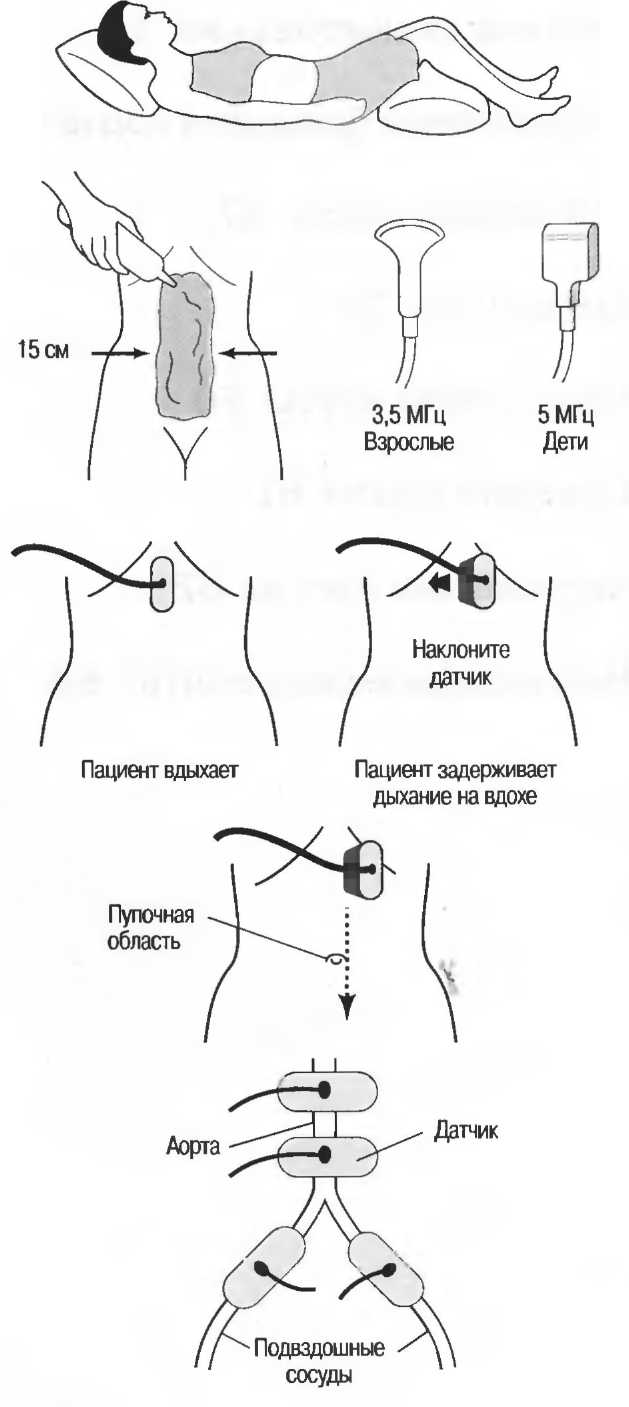

Выбор соответствующего датчика

Наилучшим датчиком для общей практики является конвексный датчик с частотой 3,5 МГц с фокусировкой на расстоянии 7-9 см. Если такого датчика нет, необходимо наличие линейного секторного датчика с частотой 3,5 МГц. При необходимости исследования детей и худых взрослых желательно дополнить набор датчиком с частотой 5 МГц с фокусировкой 5-7 см.

1. Ультразвуковые исследования в акушерстве. Для общих исследований в акушерстве используется линейный или конвексный датчик с частотой 3,5 или 5 МГц с глубиной фокусировки на 7-9 см. Если закупается только один датчик, выбирайте датчик с частотой 3,5 МГц. Датчик с частотой 5 МГц предпочтителен на ранних сроках беременности. В поздние сроки беременности лучше использовать датчик с частотой 3,5 МГц.

2. Ультразвуковые исследования в общей практике. Если проводятся исследования в верхней части живота и таза у взрослых, в том числе и акушерские исследования, предпочтительнее выбор секторного или конвексного датчиков с частотой 3,5 МГц с глубиной фокусировки на 7-9 см.